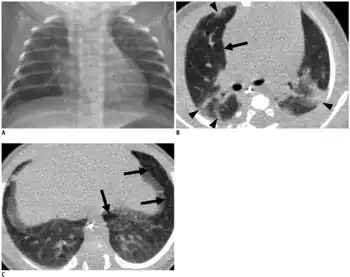

| An X-ray showing bronchopulmonary dysplasia. Person is also intubated and has an oral gastric tube. | |